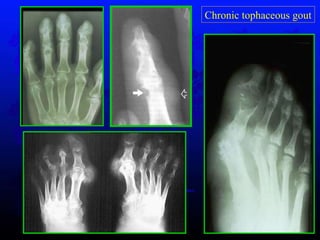

Characters * chronic polyarticular gout  * without pain-free intercritical periods * average of 11.6 years  * severe crippling disease Chronic tophaceous gout GOUT

Chronic tophaceous gout GOUT

Chronic tophaceous gout